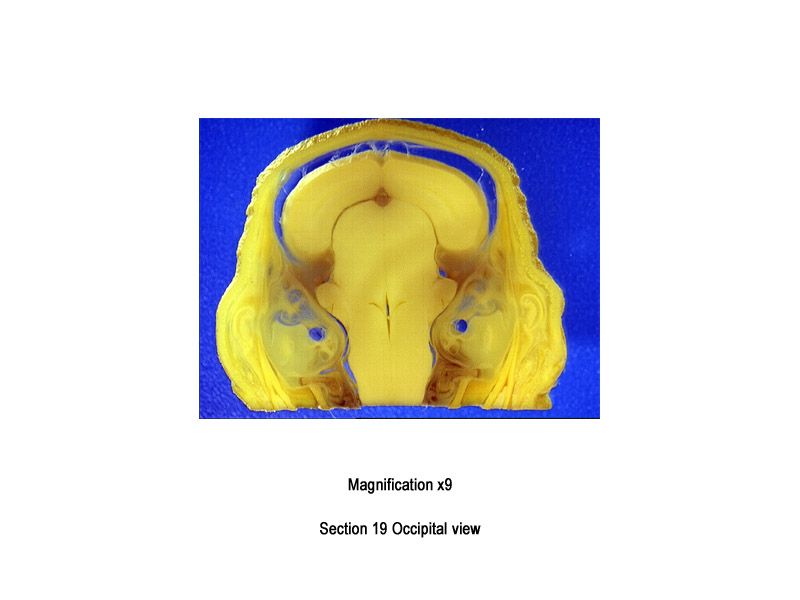

The images below show the normal appearance of Bouin's fluid fixed head sections in specimens at Day 29 of gestation (day mating observed = Day 0).

It is essential that both sides of each section is examined so that structures that exist is several sections can be visualised by the examiner in their mind as 3D.